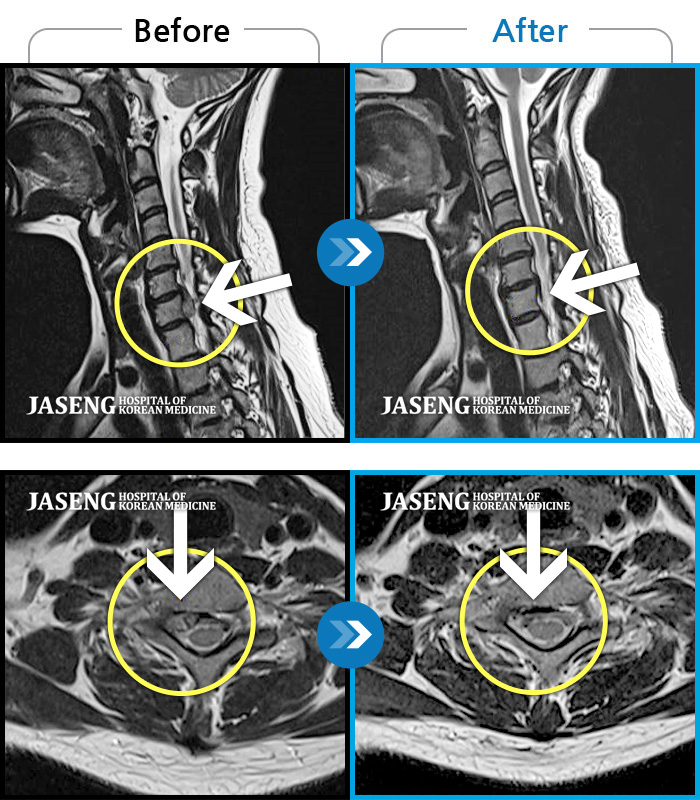

Before

After

우측 허리 뻐근한 통증, 우측 허벅지부터 발목까지 이어지는 당김

2023.03.07 ~ 2023.12.23